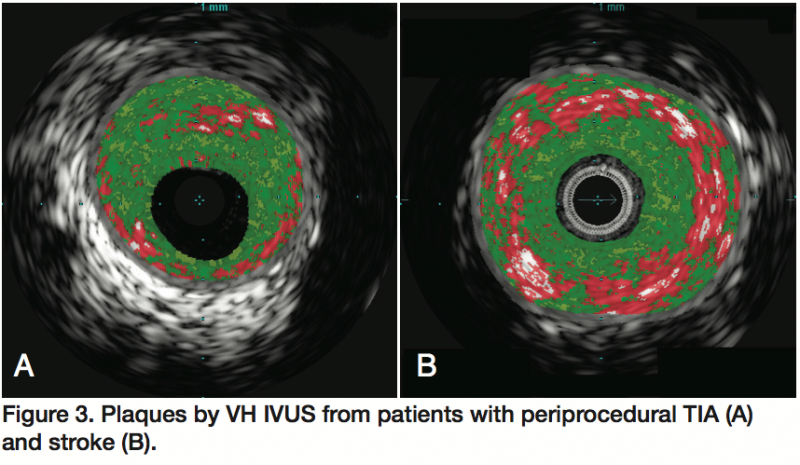

Representative VH IVUS plaque types are shown in Figures 1 and 2. There was 1 major ipsilateral stroke resulting in hemiplegia occurring the day after carotid artery stenting in a patient with FA plaque by VH IVUS. This patient had prior carotid endarterectomy with sequential stenoses of the common and internal carotid artery and was symptomatic before her CAS. There were 2 ipsilateral TIAs occurring immediately postprocedure. In one case, the plaque was a CaTCFA; the lesion was greater than 90%, heavily calcified, and a concomitant stenosis with dystrophic calcification of the cavernous segment was present. The second ipsilateral TIA was in an octogenarian with FA. VH IVUS plaques for these 3 patients with periprocedural TIA/stroke are presented in Figures 1D and 3.